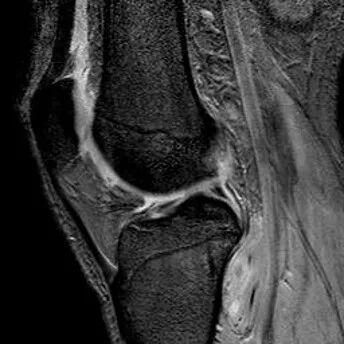

1、宽度减小,在通过半月板体部的冠状面上蝶形消失,同时可见内移的半月板位于髁间窝、交叉韧带旁2、矢状面示残余的前角或后角变小或截断3、半月板前(后)角增宽或双半月板前(后)角征4、双前交叉韧带或双后交叉韧带征

桶柄状撕裂:宽度减小,在通过半月板体部的冠状面上蝶形消失,同时可见内移的半月板位于髁间窝、交叉韧带旁

桶柄状撕裂:半月板后角增宽